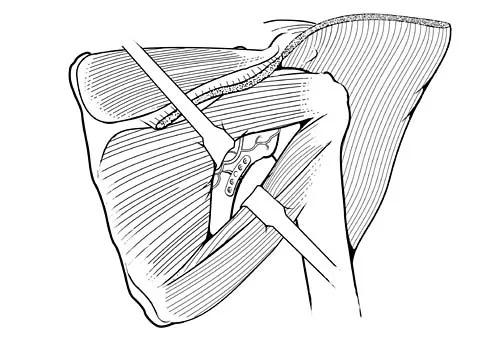

During a posterior approach to the glenoid with retraction as shown in Figure 33, care should be taken during superior retraction to avoid injury to which of the following structures?

Explanation